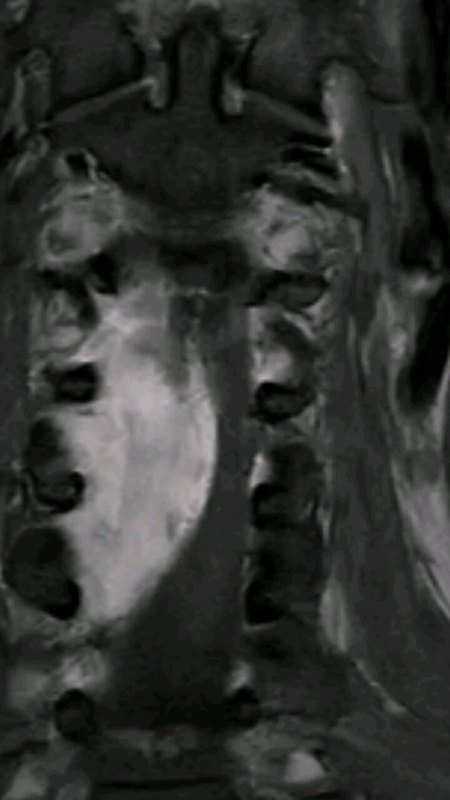

治療前病人是一位64歲的阿姨,在當(dāng)?shù)蒯t(yī)院檢查發(fā)現(xiàn)胸9水平脊髓腫瘤,根據(jù)影像學(xué)特征,考慮脊膜瘤可能性很大治療中仔細(xì)分析影像學(xué)資料,可以發(fā)現(xiàn)腫瘤占據(jù)了胸9水平椎管內(nèi)空間的90%以上,正常脊髓受壓非常嚴(yán)重,被腫瘤推擠到右側(cè)不到10%的空間。腫瘤的基底在左側(cè)硬脊膜,術(shù)中先電凝切斷腫瘤基底部的血供。從技術(shù)上來(lái)說(shuō),切除腫瘤不困難,手術(shù)的難點(diǎn)和關(guān)鍵在于切除腫瘤的同時(shí),必須要保護(hù)好第九胸椎水平菲薄的正常脊髓組織。我們?cè)陲@微鏡下先充分銳性分離腫瘤周?chē)闹刖W(wǎng)膜,然后在正常脊髓無(wú)張力的情況下分塊切除腫瘤,腫瘤全部切除。腫瘤與正常脊髓之間的膜性結(jié)構(gòu)完整保留。治療后治療后即刻切除腫瘤后,正常脊髓組織、神經(jīng)根以及被腫瘤推擠移位的脊髓血管完好保留。術(shù)后麻醉蘇醒,病人四肢肌力5級(jí),無(wú)任何神經(jīng)功能障礙。

脊膜瘤是起源于椎管內(nèi)硬脊膜的蛛網(wǎng)膜內(nèi)皮細(xì)胞或軟/硬腦膜纖維細(xì)胞的良性腫瘤,占椎管內(nèi)腫瘤的25%~46%,好發(fā)于胸段,其次為頸段,好發(fā)于中老年女性。脊膜瘤一般生長(zhǎng)較為緩慢,常對(duì)脊髓造成壓迫,引起脊髓水腫、缺血以及神經(jīng)纖維變性,從而導(dǎo)致脊髓損害。脊膜瘤患者早期最主要的癥狀為持續(xù)性疼痛,呈局灶性分布或放射狀,多為進(jìn)行性加重的銳性疼痛,于夜間及勞累時(shí)加重。隨著腫瘤繼續(xù)生長(zhǎng),肌力下降、感覺(jué)異常、步態(tài)失調(diào)等癥狀,嚴(yán)重者可導(dǎo)致患者癱瘓,應(yīng)引起充分重視。脊髓腹側(cè)腫瘤是根據(jù)腫瘤與脊髓位置關(guān)系,位于脊髓腹側(cè)時(shí)鐘位9點(diǎn)到下午3點(diǎn)鐘位置的腫瘤,包括位于脊髓側(cè)腹面及正腹前方的脊膜瘤、腸源性囊腫等。脊髓腹側(cè)脊膜瘤位置位于脊髓前方,脊髓受壓張力較高,手術(shù)切除過(guò)程中可能對(duì)脊髓功能造成影響,所以手術(shù)難度也比較大。脊膜瘤首選治療方式是手術(shù)切除,多數(shù)脊膜瘤為良性,在手術(shù)切除后可得到徹底治愈。對(duì)于脊髓腹側(cè)脊膜瘤,因有脊髓的遮擋,切開(kāi)椎板后不能直視腫瘤。術(shù)中需要盡可能擴(kuò)大椎管骨性結(jié)構(gòu),甚到磨除腫瘤相應(yīng)部位關(guān)節(jié)突關(guān)節(jié),若腫瘤處于椎弓根水平則需要磨除椎弓根,正腹方脊膜瘤有時(shí)需要磨除雙側(cè)椎弓根來(lái)擴(kuò)大下一步操作空間。在擴(kuò)大切除椎管內(nèi)側(cè)壁骨性結(jié)構(gòu)的基礎(chǔ)上,獲得對(duì)腫瘤的直視視野極為重要。只有在直視下,才能準(zhǔn)確判斷腫瘤與脊髓粘附程度,方便后續(xù)手術(shù)操作。手術(shù)力求從脊髓側(cè)方進(jìn)入,為盡量減輕對(duì)脊髓的壓迫和被迫移位,盡量分塊切除腫瘤。腫瘤將脊髓擠壓至椎管后部,切開(kāi)硬脊膜時(shí)應(yīng)該十分小心,注意避免誤傷脊髓。由于腫瘤位于脊髓腹側(cè),脊髓或神經(jīng)往往處于較大張力下,而手術(shù)亦是從側(cè)后方操作,切斷數(shù)條脊髓齒狀韌帶,松解脊髓以利于脊髓被動(dòng)移位。脊膜瘤手術(shù)切除能獲得良好的治療效果,關(guān)鍵在于早期發(fā)現(xiàn),早期治療。典型脊髓腹側(cè)脊膜瘤患者,術(shù)前已出現(xiàn)明顯的脊髓壓迫癥狀,雙下肢無(wú)力,不能行走。術(shù)后復(fù)查磁共振顯示腫瘤已經(jīng)完全切除,患者雙下肢無(wú)力癥狀明顯改善。